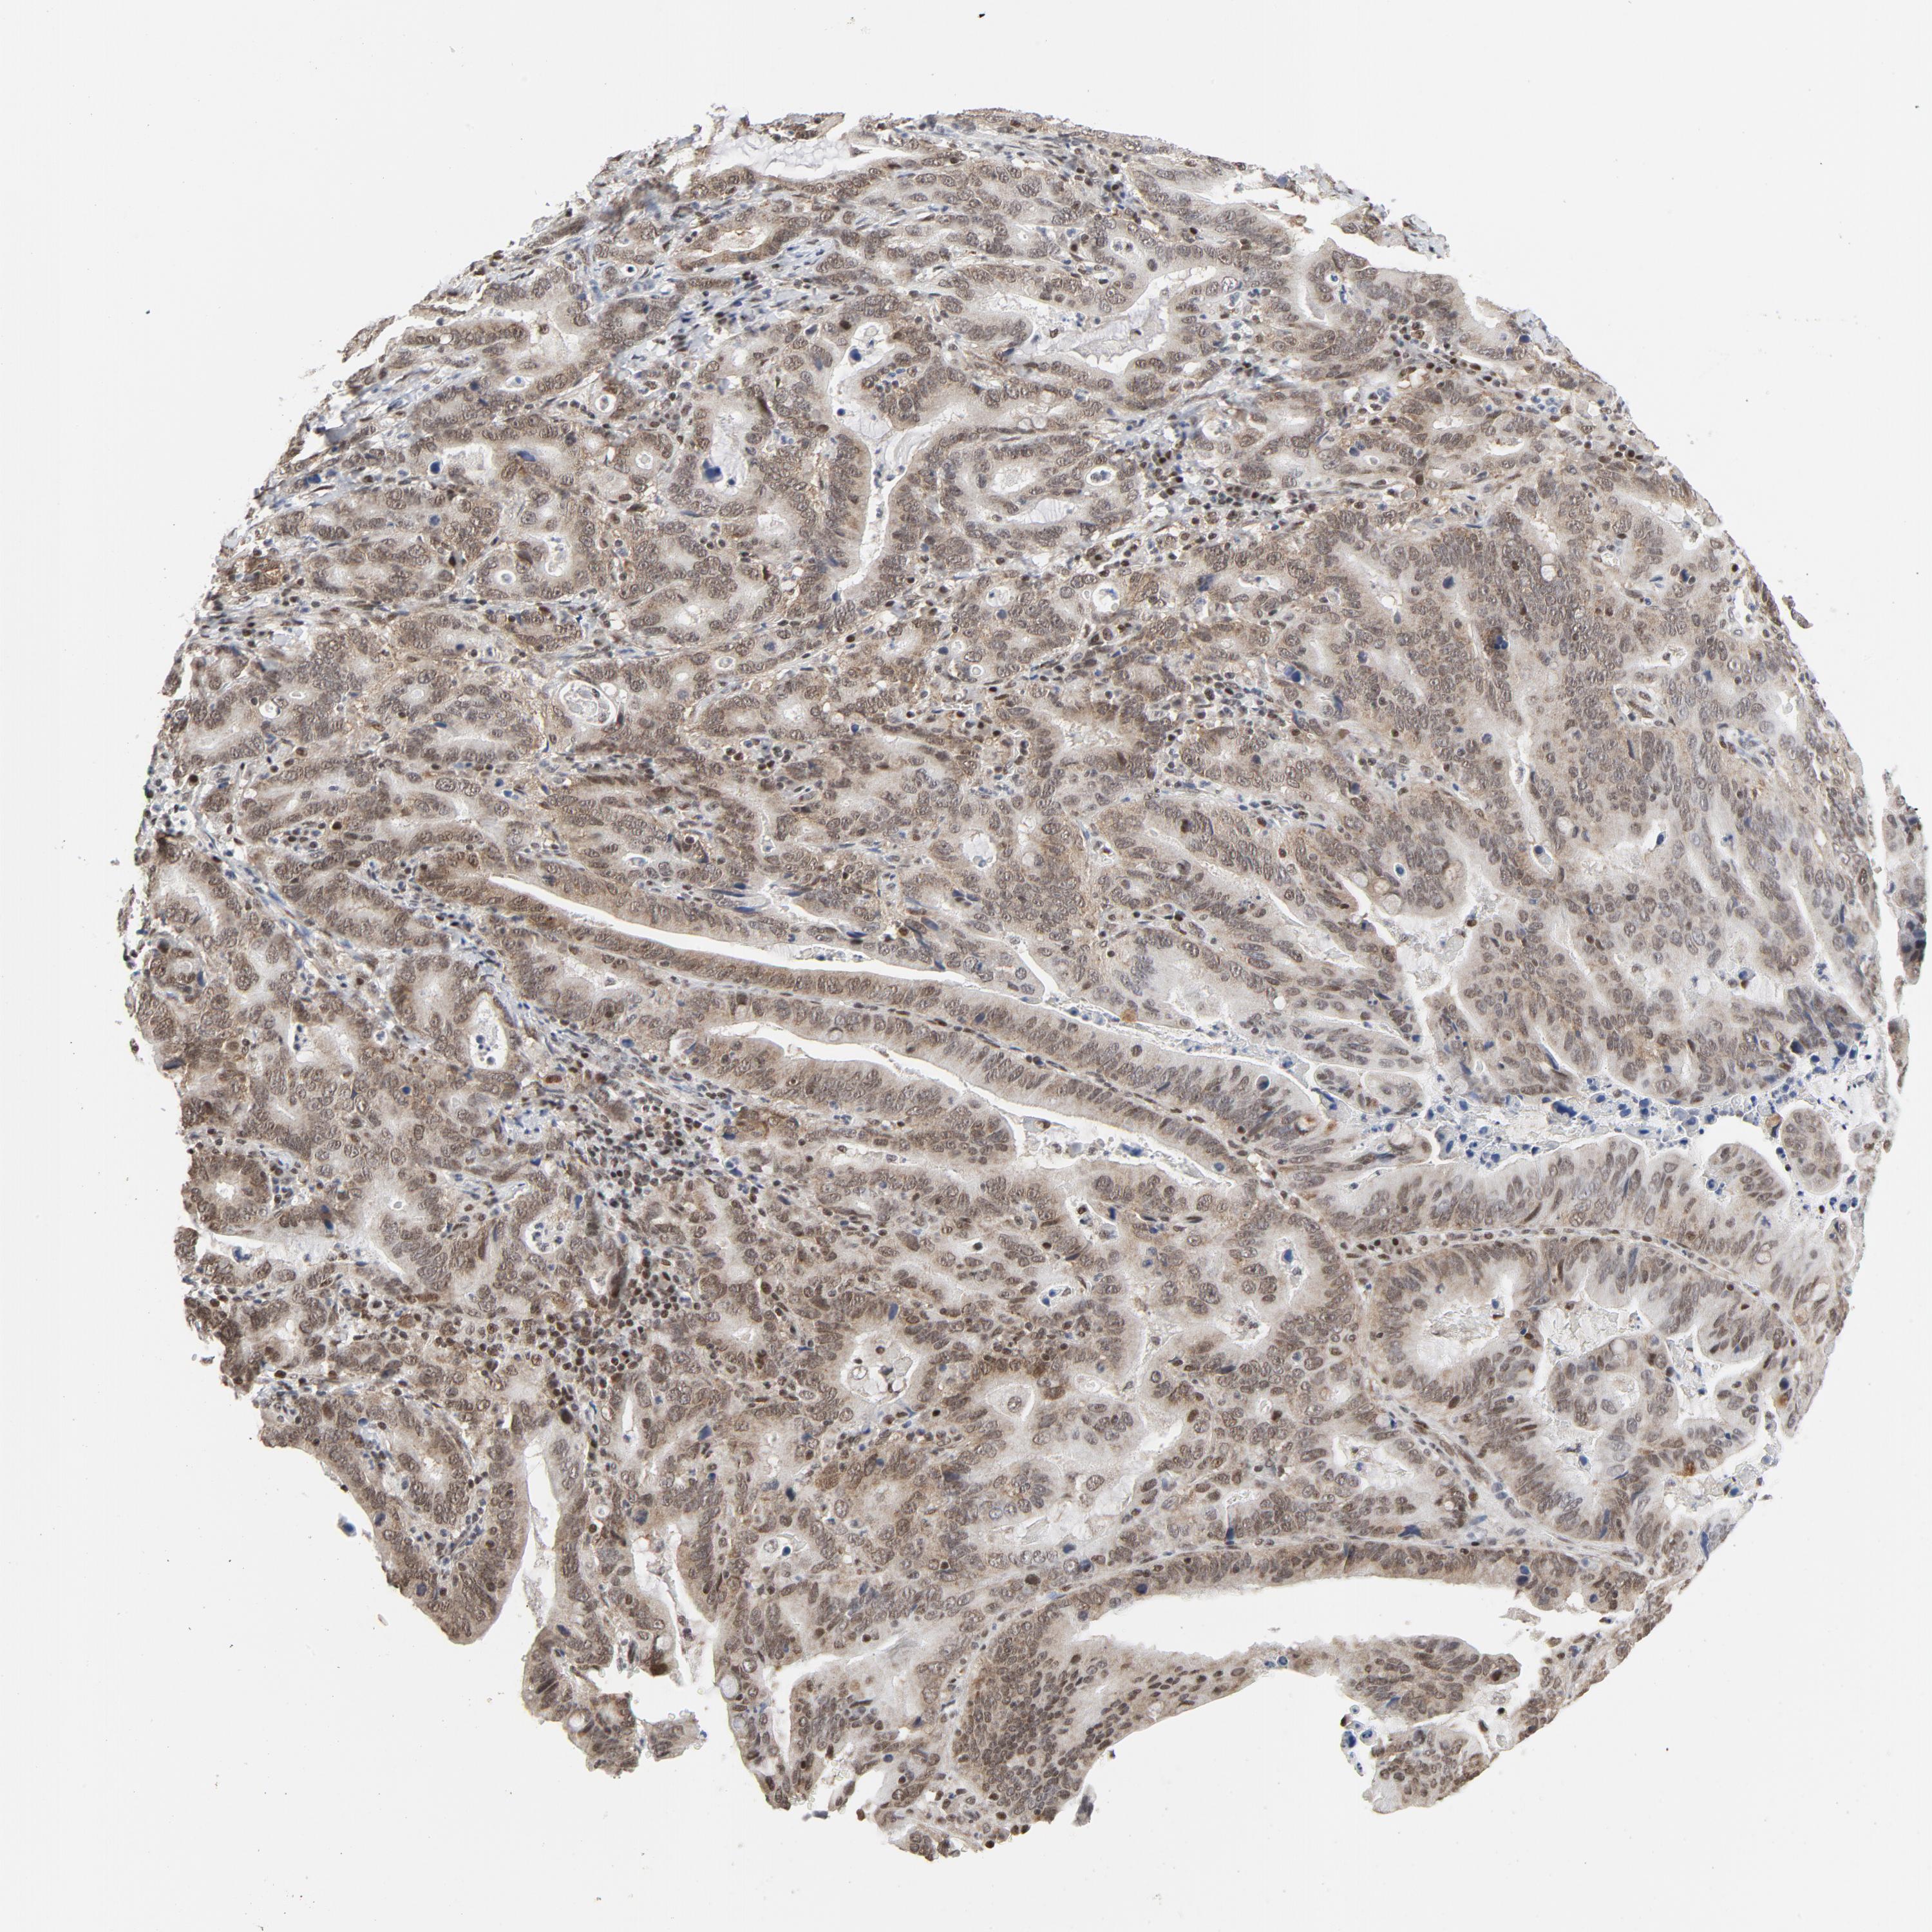

STOMACH CANCER - Protein expressioni

A mouse-over function shows sample information and annotation data. Click on an image to view it in a full screen mode. Samples can be filtered based on level of antibody staining by selecting one or several of the following categories: high, medium, low and not detected. The assay and annotation is described here.

Note that samples used for immunohistochemistry by the Human Protein Atlas do not correspond to samples in the TCGA dataset.

Antibody stainingi

Antibody staining in the annotated cell types in the current human tissue is reported as not detected, low, medium, or high, based on conventional immunohistochemistry profiling in selected tissues. This score is based on the combination of the staining intensity and fraction of stained cells.

Each image is clickable and will lead to virtual microscopy that enables deeper exploration of all samples and also displays staining intensity scores, fraction scores and subcellular localization as well as patient and tissue information for each sample.

Antibody HPA029773

Antibody CAB004390

Antibody CAB072859

Antibody CAB072860

Staining

High

Medium

Low

Not detected

Intensity

Strong

Moderate

Weak

Negative

Quantity

>75%

75%-25%

<25%

None

Location

Nuclear

Cytoplasmic/membranous

Cytoplasmic/membranous,nuclear

Adenocarcinoma, NOS